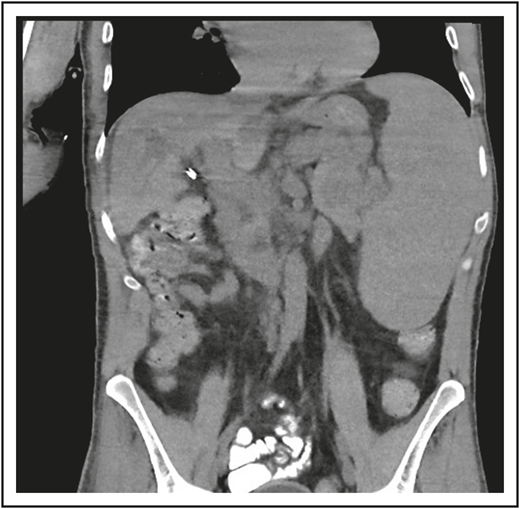

A third common reason for hematologists to see patients with CVID is a suspicion of lymphoma. Patient 3 is now a 47-year-old computer executive who came for a second opinion to the immunology department. He had had numerous sinopulmonary infections in childhood and then 2 episodes of shingles in his 30s. At the age of 36, he had acute AIHA treated with steroids. He then had an episode of cellulitis, and, with this, serum immunoglobulins were tested, which showed quite low levels: IgG, 186 mg/dL; IgA, 9 mg/dL; and IgM, 24 mg/dL. At the same time, his spleen was quite large. He was diagnosed with CVID, and immunoglobulin therapy was initiated. Owing to the enlarged spleen, now at 19 cm, a bone marrow biopsy was performed, and he was ultimately seen at another center at the age of 42, when the diagnosis of marginal zone lymphoma was made on the basis of bone marrow findings. He was treated with 6 cycles of rituximab and bendamustine. However, his splenomegaly persisted, and 3 years later, he sought an opinion at another medical center, where he was told that he did not have lymphoma on the basis of National Cancer Institute review of his bone marrow. Now, 5 years later, he has been well while receiving intravenous immunoglobulin, but he continues to have an enlarged spleen. There are no signs of lymphoma (Figure 3).

The patient in clinical case 3 was concerned because after he received chemotherapy for a presumed lymphoma, his spleen remained large. However, this is typical in patients with CVID.